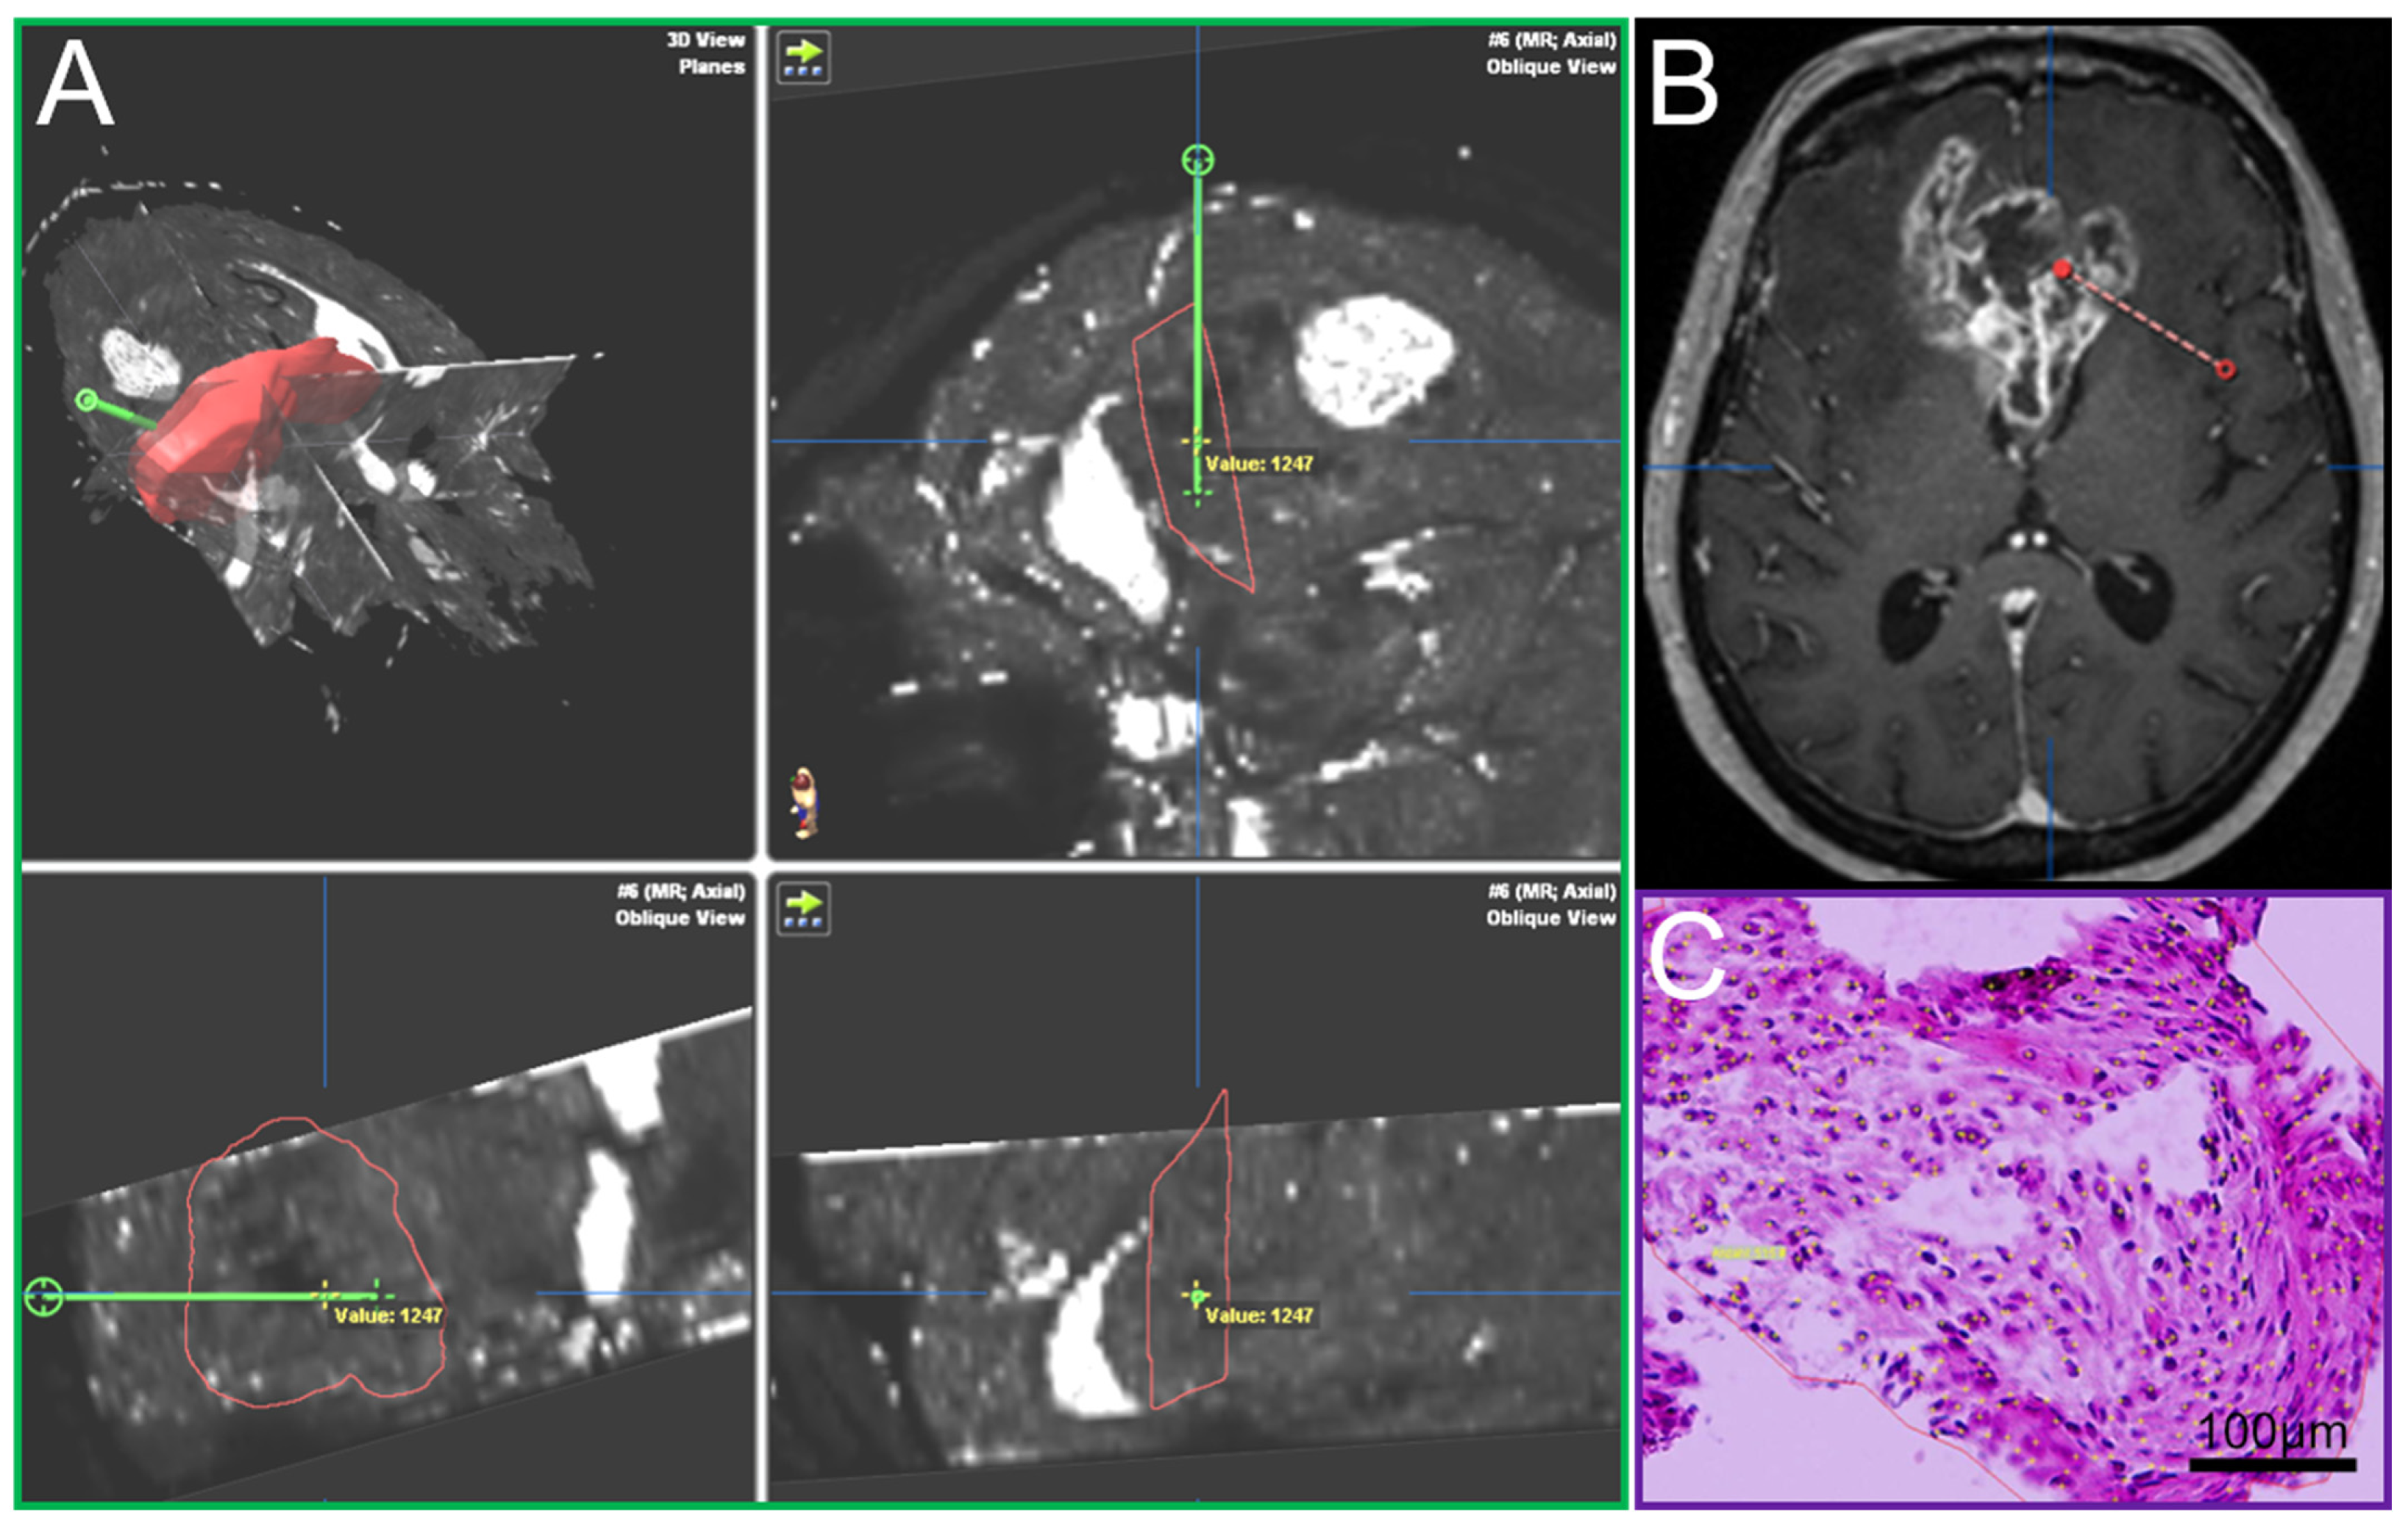

The assignment of local relaxation times to different biopsy samples was performed with the Brainlab iPlan system (BrainLab iPlan 1.0, Munich, Germany).

2.3. Surgical Procedure, Histopathology and MRI Matching

A Leksell (Leksell® Coordinate Frame G, Elekta Instruments, Stockholm, Sweden) stereotactic frame was attached to the patients’ head prior to burr hole surgery and fixed with four screws (two frontal and two occipital). A CT scan was performed and fused to the MRI. The trajectory was calculated using the BrainLab iPlan system and the localization of each specimen was documented as it was taken on this preplanned trajectory [15]. Such frame-based biopsies have an accuracy within the range of 1–2 mm [22]. In most cases a standard 12 mm burr hole was performed. In order to avoid brain shift the dura was only opened minimally to accommodate the 2.1 mm guide for the biopsy forceps. The number of specimens taken in a tangential manner from tumor areas showing contrast enhancement in MRI [23] and the location of the trajectory were at the discretion of the neurosurgeon in charge and varied due to clinical aspects including the size, the configuration and the location (e.g., eloquent area) of the lesion. The primary aim of the procedure was to confirm the tumor diagnosis employing histology, immunohistochemistry and molecular pathology. An important aspect was the feedback of the neuropathologist’s intra-operative smear-pathology assessment. Up to 23 tissue samples with a volume of 1 mm3 in 1 mm steps along the biopsy trajectory were obtained, fixed in 4% paraformaldehyde and paraffin embedded. Sections with a thickness of 3 µm were cut on a Leica SM 2000R microtome (Leica Biosystems, Wetzlar, Germany), mounted on microscope slides (SuperFrost Plus, Thermo Scientific, Waltham, MA, USA) and subjected to HE staining. The O6-methylguanine-DNA methyltransferase (MGMT) promoter methylation status was determined by methylation-specific polymerase chain reaction [24]. Immunohistochemistry against isocitrate dehydrogenase (IDH)1_R132H (mouse monoclonal, clone DIA-H09, concentration 1:50, Dianova, Hamburg, Germany), lactate dehydrogenase A (LDHA, Clone C4B5 #3582S, Cell Signaling Technology, Danvers, MA, USA), carbonic anhydrase IX (CAIX, #NB100-417, Novus Biologicals, Littleton, CO, USA) and Ki67 (Clone MIB-1, Dako, Glostrup, Denmark) was performed according to standardized protocols using a Leica BOND-III stainer. The analysis, including cell and vessel counts and the assessment of necrosis on the basis of HE stained sections, was performed by blinded examiners on an Olympus BX41 microscope (Olympus, Tokio, Japan). Pictures were taken with an Olympus DP72 camera and analySIS software provided by Olympus. Cell and vessel density was calculated as the number of cells and vessels per mm2. The amount of necrosis (%) was assessed by estimating necrotic areas in relation to the whole tissue area on HE stained slides. The amount of CAIX and LDHA positive areas was determined by estimation of positive stained area in relation to the whole tissue area. Cells stained positive for Ki67 were recorded as percentages of total cellularity. For each sample, it was documented whether vascular proliferates were present or absent. Each tissue probe was correlated with its specific location on the trajectory and the resulting defined position in the MRI data using the BrainLab iPlan system (Figure 1). By doing so, individual quantitative relaxation times were assigned to each biopsy sample.

Figure 1.

(A) T2′ maps with trajectory (green, iPlan BrainLab), (B) Conventional MRI, contrast-enhanced T1, axial plane, with trajectory (red), (C) Hematoxylin-eosin stain of a biopsy sample.